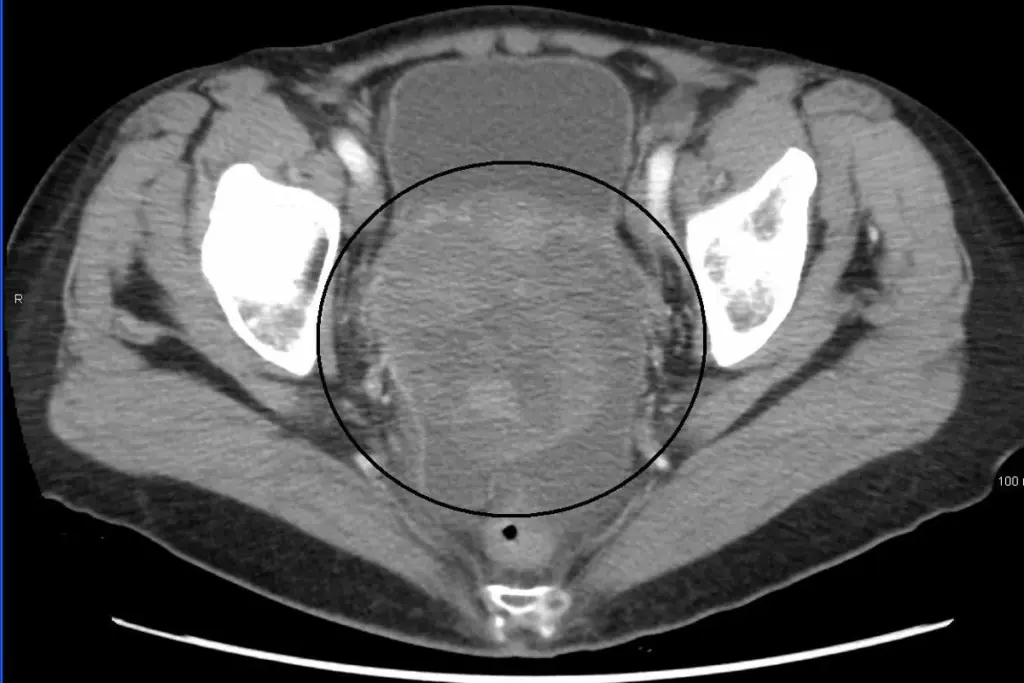

<image2>

Diet and cancer treatment outcomes are closely linked for ovarian cancer patients. Nutrition is key in supporting the body during treatment. It can improve outcomes and lower malnutrition risk.